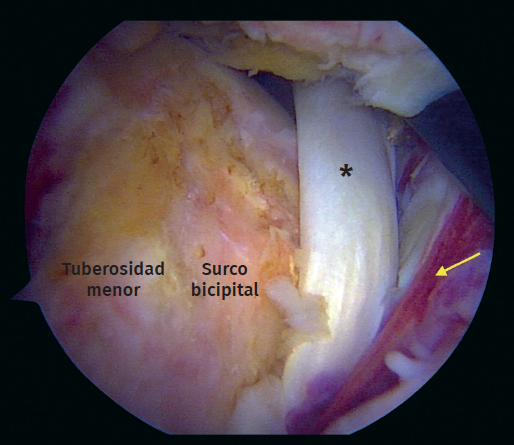

Figura 5. Vista artroscópica. Rotura completa del subescapular con inestabilidad medial de la cabeza larga del tendón del bíceps. Asterisco: tendón del bíceps. Flecha: rotura del tendón subescapular.

Durante el periodo descrito, se intervino a un total de 15 pacientes que cumplían con los criterios de inclusión. Se excluyó a un paciente debido a que el tiempo de seguimiento era insuficiente. Se incluyeron un total de 14 pacientes (Tabla 1), con una edad promedio de 65 años (rango de 46 a 76 años), 8 de los cuales eran hombres (57%). El tiempo promedio de seguimiento fue de 29,4 meses (rango de 24 a 41 meses). De los 14 pacientes evaluados, 13 (92,8%) presentaban algún compromiso del bíceps proximal como roturas parciales, lesiones degenerativas o inestabilidad medial (Figura 5). Se realizó una tenotomía del bíceps en 9 pacientes (64,2%), una tenodesis intraarticular en 2 casos (14,2%) y se detectó una rotura crónica del bíceps en 2 pacientes (14,2%). En la mitad de los pacientes (7) la rotura subescapular se reparó con 2 anclajes con nudo y en los restantes, con una fijación híbrida utilizando un anclaje superior con nudo y un anclaje inferior sin nudo con cintas de sutura (Tabla 2).